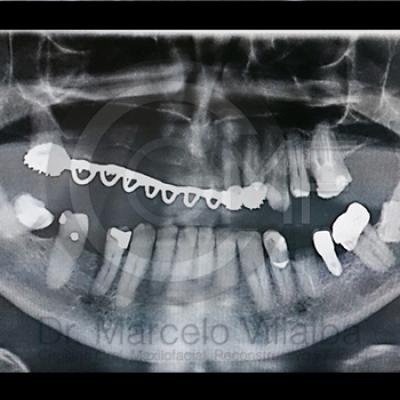

Generalmente en el momento de su erupción presentan procesos inflamatorios en la zona posterior de la cavidad oral, infección, dolor, movilidad de órganos dentarios, mal sabor en boca, mal olor en boca (halitosis), infección, incluso edema (aumento de volumen en tejido blando de la cara y/o boca) y complicaciones si no son atendidos. En el apoyo de diagnóstico se pueden requerir radiografías panorámicas y hasta tomografía en caso de ser necesarios.

Para el tratamiento de estas patologías se necesita en forma inicial estudios de laboratorio, radiografías o tomografías, estos estudios serán solicitados por el especialista a cada caso en particular, siendo su tratamiento quirúrgico bajo la modalidad de anestesia local o anestesia local más sedación consciente se puede realizar el procedimiento en corto tiempo y buen pronóstico.